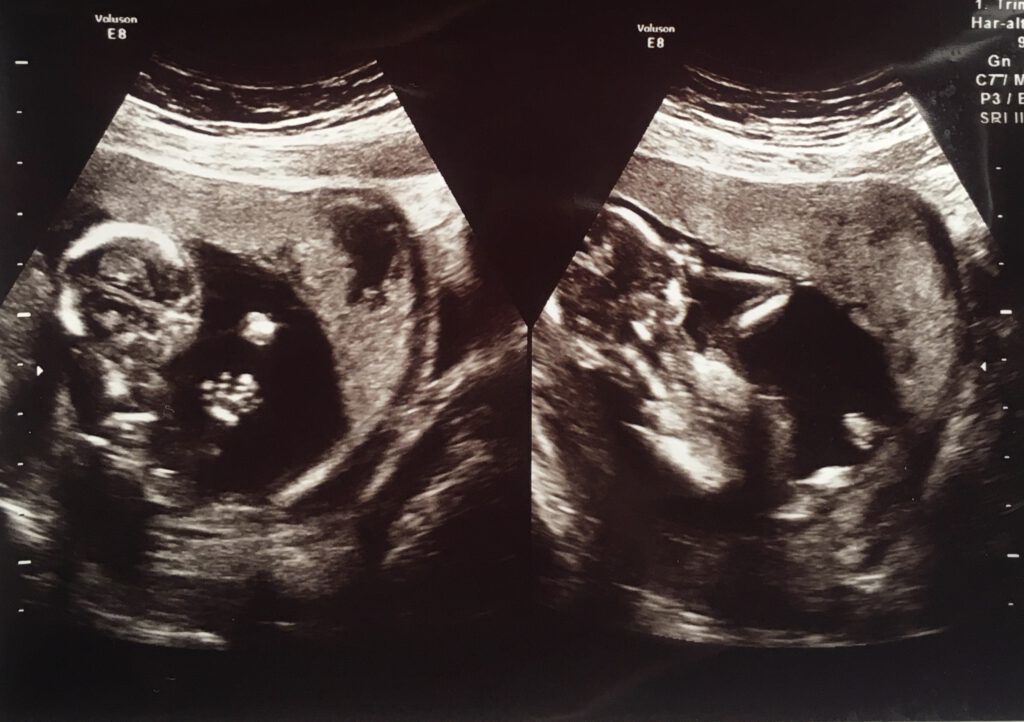

Siguiendo con el latido del embrión… A las siete semanas llegó el momento esperado. En estos casos no se utiliza un estetoscopio, sino un sistema de ultrasonido con amplificadores de onda. El sonido que yo me esperaba llegó desde unas bocinas invisibles que intenté localizar hasta que la imagen apareció y pude observar una forma de onda muy compacta. Mis deducciones cedieron al latido. El sonido era más rápido de lo que esperaba, sobre todo pensando que el embrión tenía el tamaño de una zarzamora. Me recordó a un papel arroz que se desvanece cuando es lamido.

Fue muy grato saber que nuestro embrión estaba saludable, pero el sonido mismo no me generó mayor interés. Le comenté a la doctora que escuchaba ciertas arritmias y ella se burló de mí, tomó mi comentario como una broma. Lloré, desde luego, aunque quizá lo hice más por seguir el protocolo. Isabel sí lloró con especial emoción: claro, ella lo lleva dentro, una pequeña locomotora en su vientre.